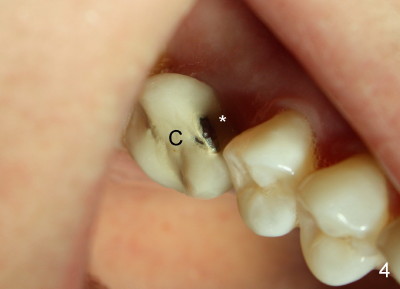

After crown cementation, the patient moves to Washington DC. She returns on vacation to replace PFM crown (Fig.4 C) with chip (*). Fig.5 shows a new Emax crown (C) after cementation. What is the most troubling is that there is cracking sound during cementation. The patient calls from DC, reporting that there is minor chipping. It is planned to fabricate a Zirconia crown next time she returns for visit in Atlanta.

Fig.6 and 7 show the die in buccal and mesial views, respectively. Red arrowheads in Fig.7 indicate the crown margin that rests on the implant, whereas the white arrowheads point to the junction of the implant and the abutment. It appears that the height of the abutment is approximately 2 mm (B: buccal).